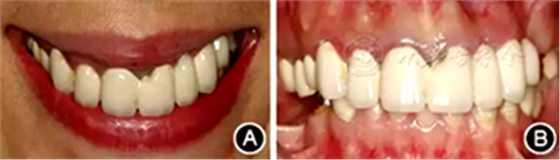

口腔衛(wèi)生狀況一般,菌斑指數(shù)0~2,鄰面少量軟垢;牙齦齦緣鮮紅、水腫、質軟,出血指數(shù)2~3,余牙牙齦輕度水腫,出血指數(shù)0~2;全口探診深度2~3 mm,個別位點探診深度達4~5 mm,鄰面可探及附著喪失;未查及牙齒松動及根分叉病變;烤瓷固定橋修復,冠邊緣密合度欠佳,位于齦下1~2 mm;、唇側崩瓷,邊緣暴露;上前牙牙齦線不協(xié)調(diào);缺失,右下后牙可摘局部義齒修復,固定橋修復;近中面銀汞充填,近中懸突及繼發(fā)齲;上前牙覆蓋下前牙牙冠的1/2~2/3(圖1)。

圖1 患者初診時臨床照片 A:正面微笑像;B:正面口內(nèi)像